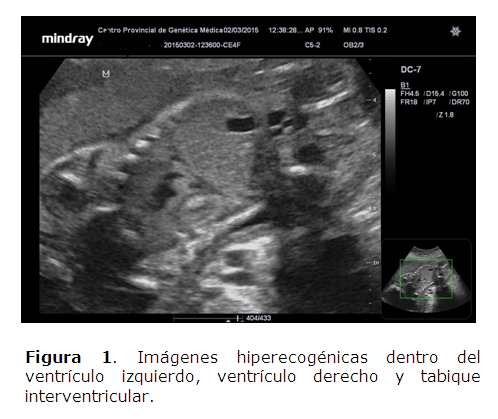

Se le realizó ultrasonido que informó: feto único, con buena vitalidad, líquido amniótico normal, placenta anterior. Nos llamó la atención la presencia de múltiples imágenes hiperecogénicas dentro del ventrículo izquierdo, ventrículo derecho y tabique interventricular que siguen los movimientos de contractilidad del musculo cardíaco; se localizó el mayor de esta imágenes en el tracto de salida del ventrículo izquierdo, sin otras alteraciones morfológicas fetales (Figuras 1).

Clínicamente pueden asociarse a un derrame pericárdico y ecográficamente se presentan como lesiones sésiles de ecogenicidad mixta. Los mixomas cardiacos fetales son excepcionales, a diferencia de lo que ocurre en los tumores cardiacos primarios del adulto. Su comportamiento suele ser bifásico, con un crecimiento progresivo hasta la semana 32 de gestación, y posteriormente tiende a reducirse progresivamente durante los dos primeros años de vida. Los rabdomiomas pueden ser localizados o multifocales, suelen aparecer en el tabique interventricular o en la pared libre ventricular y auricular. Su apariencia ecográfica es la de una masa redondeada hiperecogénica, bien definida.3,5,7,8 Estas características hicieron que el caso presentado fuera diagnosticado de probable rabdomioma cardiaco, aunque no se dispone de la confirmación histológica por no haberse realizado tratamiento quirúrgico.